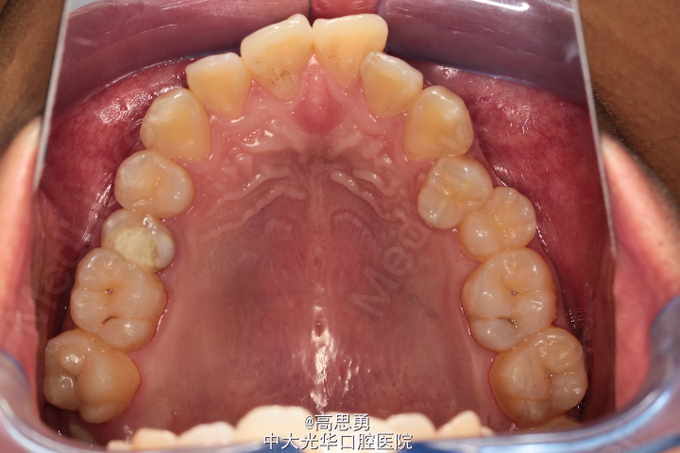

贵金属烤瓷冠一例

左上5远合面牙色暂封物,探(-),扣(-),松(-)。X线示根充可。

拟行贵金属桩核冠修复。

若患者经济能力允许,还是建议选择贵金属烤瓷冠。边缘密合性更好,发生继发龋的机会更小,修复效果更好。